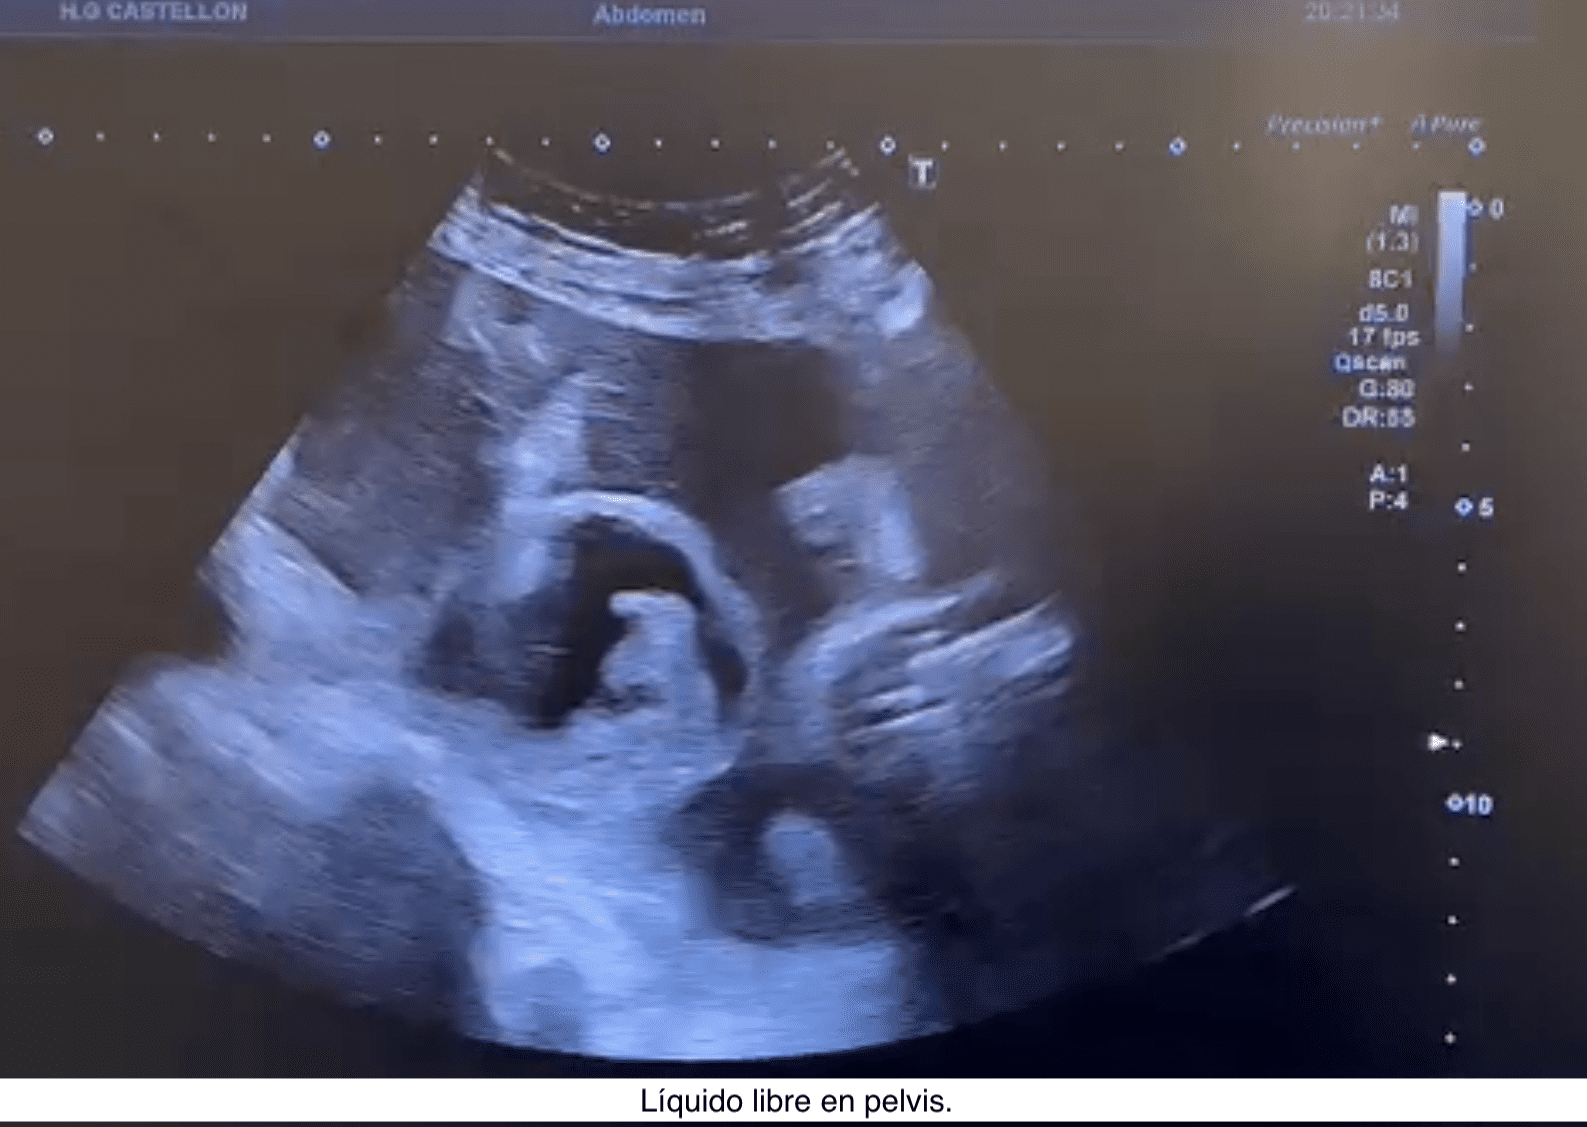

Se hace una ecografía abdominal a pie de cama, objetivando líquido ascítico junto líquido libre perihepático, periesplénico y pelvis inferior, sin otros hallazgos.